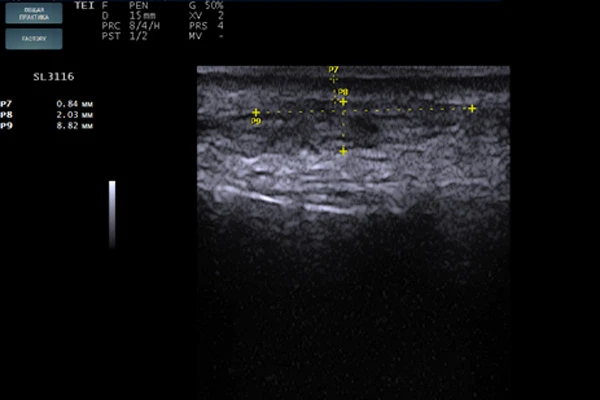

STYLAGE® HydroMax был введен в область губ и периоральной зоны комплектной иглой 30 G в линейно-ретроградной (мезоармирующей) технике. Слой введения — глубокая дерма (Рис. 1). Сразу после введения была выполнена сонограмма в зоне носогубной складки (Рис. 2). На изображении хорошо видны зоны имплантата анэхогенной структуры с ровными краями, овоидной формы, так же заметно, что ткани в этой области сдвинуты по направлению друг от друга и между дермой и мышечным слоем определяется наличие геля. На контрольной сонограмме, сделанной через 4 месяца (Рис. 3), имплант приобретает изоэхогенную структуру, в нем определяются гипоэхогенные включения, что указывает на начало процесса биодеградации и замещение импланта собственными тканями. На сонограмме 3, выполненной через 13 месяцев (Рис. 4), хорошо визуализируется участок локации импланта с границей гиперэхогенной капсулы, внутри которой определяется полное разрешение процесса биодеградации.

Сонограмма дермального имплантата

Рис. 4. Сонограмма дермального имплантата через 13 месяцев после введения